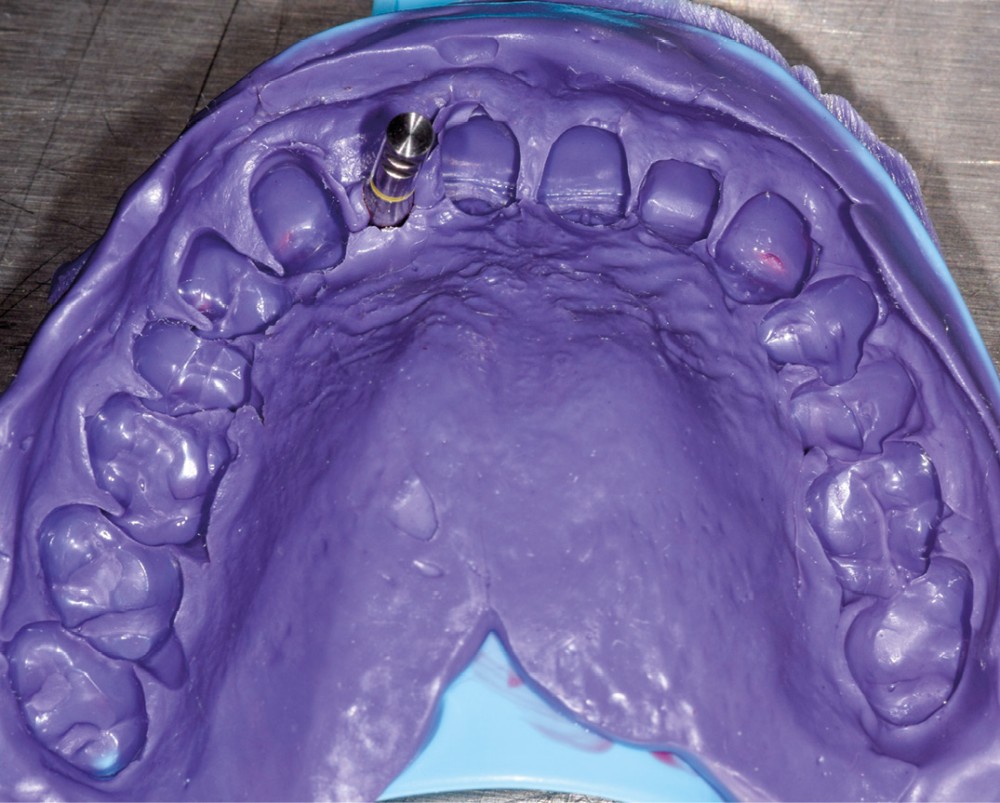

Un patient de 62 ans se présente en consultation afin de réaliser les coiffes prothétiques des dents 12 et 22. La 12 présente une restauration par prothèse transitoire non adaptée. Un implant au niveau de la 22 a été posé par un autre praticien selon une technique chirurgicale en deux temps. Le praticien a adressé le patient pour la réalisation prothétique. L’option de bridge collé cantilever mono ailette n’avait pas été retenue ou proposée selon une technique chirurgicale en deux temps. Le patient souhaite rétablir l’esthétique et la fonction de ces deux dents uniquement.

La proposition thérapeutique retenue par le patient est donc une réhabilitation par couronne céramique sur 12 (dento-portée) et 22 (implanto-portée). Ce choix thérapeutique impose de concevoir des dents qui s’intègrent au mieux dans l’harmonie du sourire, tout en étant conscient des limites d’un tel traitement.